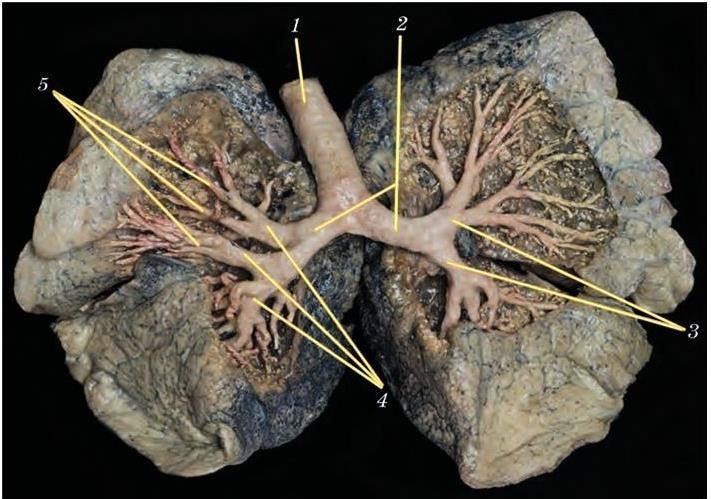

1. Severe lung damage - a life without breath

Over time, chronic inflammation and toxin buildup cause irreversible damage to the airways and lung tissue.

The lungs lose their ability to absorb oxygen efficiently. No quick remedy can restore what's been destroyed.

2. COPD progression - the silent suffocator

Untreated lung congestion and airway inflammation often develop into full-scale COPD.

It may begin with mild shortness of breath or an occasional cough-but the damage continues silently.

Before patients realize what's happening, their lung capacity has already declined significantly.

4. Heart strain and respiratory failure

COPD doesn't just affect the lungs-it places extreme stress on the heart.

Poor oxygen circulation forces the heart to work harder, increasing the risk of heart failure and respiratory collapse.